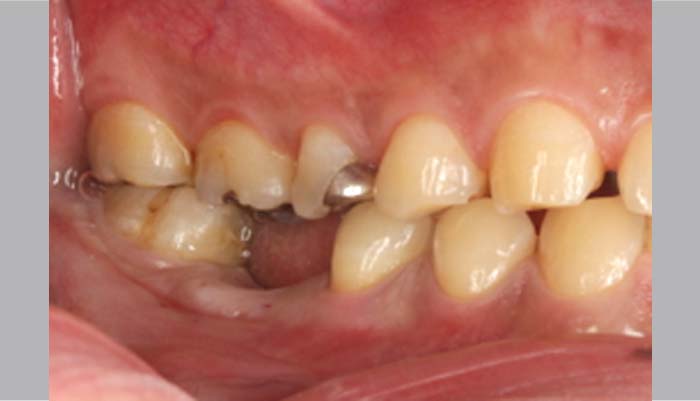

症例紹介